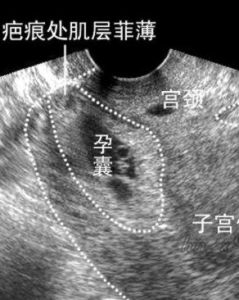

生理情況下,在孕卵著床及胎盤形成過程中,大量的滋養細胞瀰漫性浸潤胎盤床,這時子宮內膜間質轉化成富有糖原的蛻膜細胞。隨著滋養細胞浸潤越多,間質蛻膜化的程度就越大。因此,一般認為,蛻膜形成是為了抑制滋養細胞進一步的浸潤。在胎盤植入的病例中,子宮內膜間質蛻膜缺乏或有缺陷,受精卵如在此處著床,間質不能充分蛻膜化,一方面屏障作用消失,不能阻止滋養細胞的浸潤;另一方面胚胎絨毛在蛻膜化不良的組織中難以得到良好的血液供應,而發生植入。可見,子宮黏膜缺乏或缺陷是胎盤植入的病理基礎,因此,所有子宮內膜疾病都容易發生胎盤植入,包括黏膜下子宮肌瘤、子宮瘢痕、子宮肌瘤剔除術後或殘角子宮切除術後及有刮宮、徒手剝離胎盤、子宮內膜炎病史等。剖宮產術後的子宮瘢痕處內膜局部常有缺損,受精卵在此著床時也不能進行充分的蛻膜化,或原著床在正常的子宮內膜,在發育過程中,滋養細胞擴張到蛻膜化不良的子宮內膜部位。因此,孕卵在剖宮產術後瘢痕局部子宮內膜缺陷處著床時,極易發生胎盤絨毛植入。

瘢痕子宮患者前置胎盤的發生率增高近5倍,同時低置胎盤可增加胎盤植入的危險性。在一些文獻的報導 [3] 中,早孕胎盤植入的病例均有剖宮產病史。可見剖宮產術後的子宮瘢痕患者,如孕卵著床在子宮下段將來可能發展為前置胎盤,也可發生早中期妊娠的胎盤植入。

目前,我國剖宮產率增高,在早期妊娠時,胎盤絨毛植入的危險性將可能明顯增高。因此,在人工流產術或刮宮術中如遇難以控制的大出血,特別是有剖宮產史及停經後有陰道出血情況者,要高度懷疑胎盤絨毛植入,應做相應的處理,如有必要每位瘢痕子宮再孕的婦女都要B超探查絨毛的部位,避免人工流產術中難以控制的大出血和不必要的醫療糾紛。